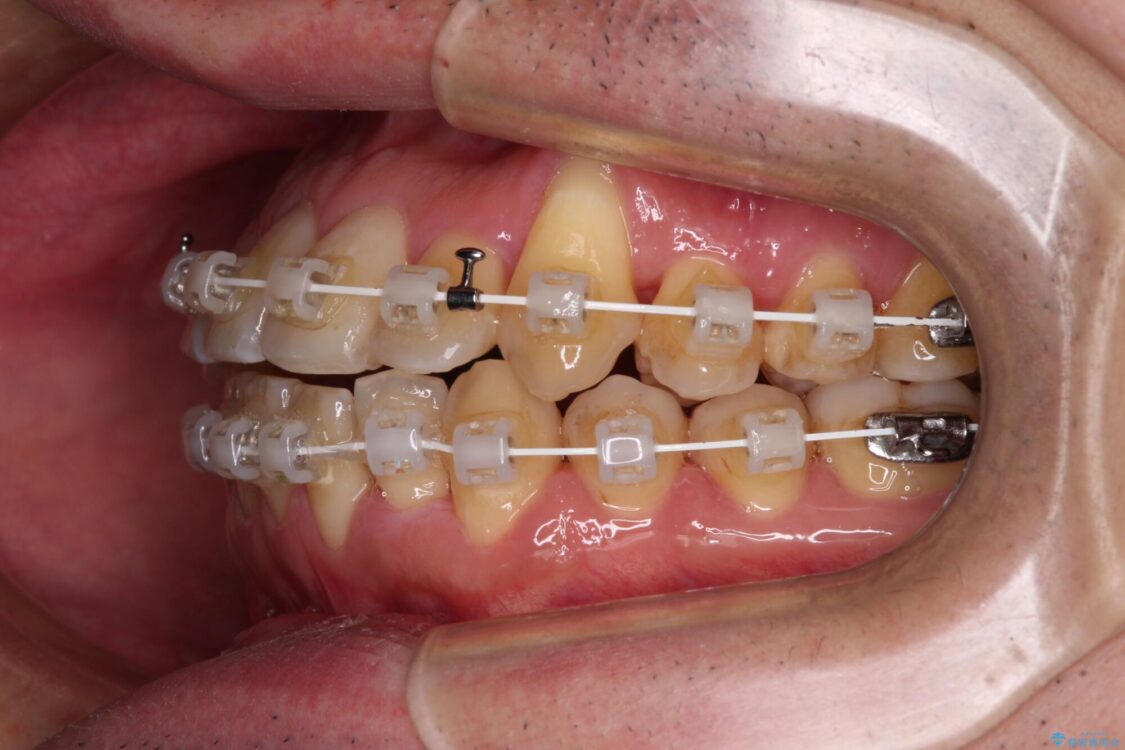

マウスピース矯正での自己管理には自信がないとのことで、ワイヤー装置による矯正治療を行うこととしました。

クロスバイトは、治療の過程で咬み合わせが大きく変化する期間があり、食事が取りにくくなってしまいます。

また、装置が対合歯と咬み合ってしまい、頻繁に脱落するなど、色々と面倒なことがあり、治療がスムーズに進まないことがあります。

治療途中

• 八重歯とクロスバイト 目立たないワイヤー装置で矯正治療 治療途中画像